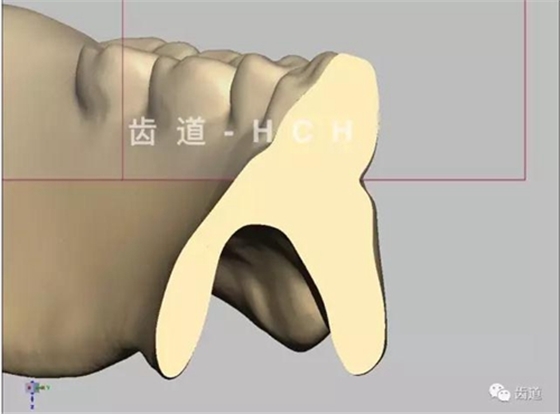

標(biāo)準(zhǔn)全口義齒模型截圖 科貿(mào)嘉友收錄